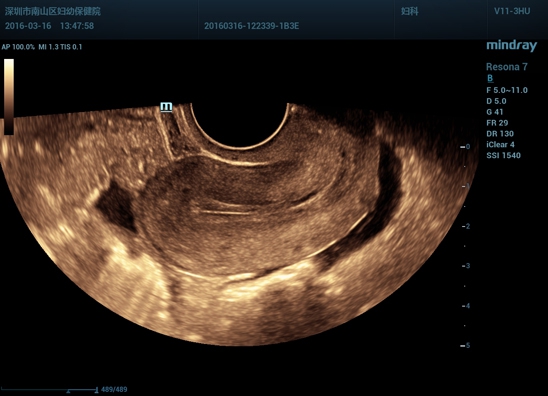

• Микроконвексный высокоплотный внутриполостной датчик Mindray V11-3Ws